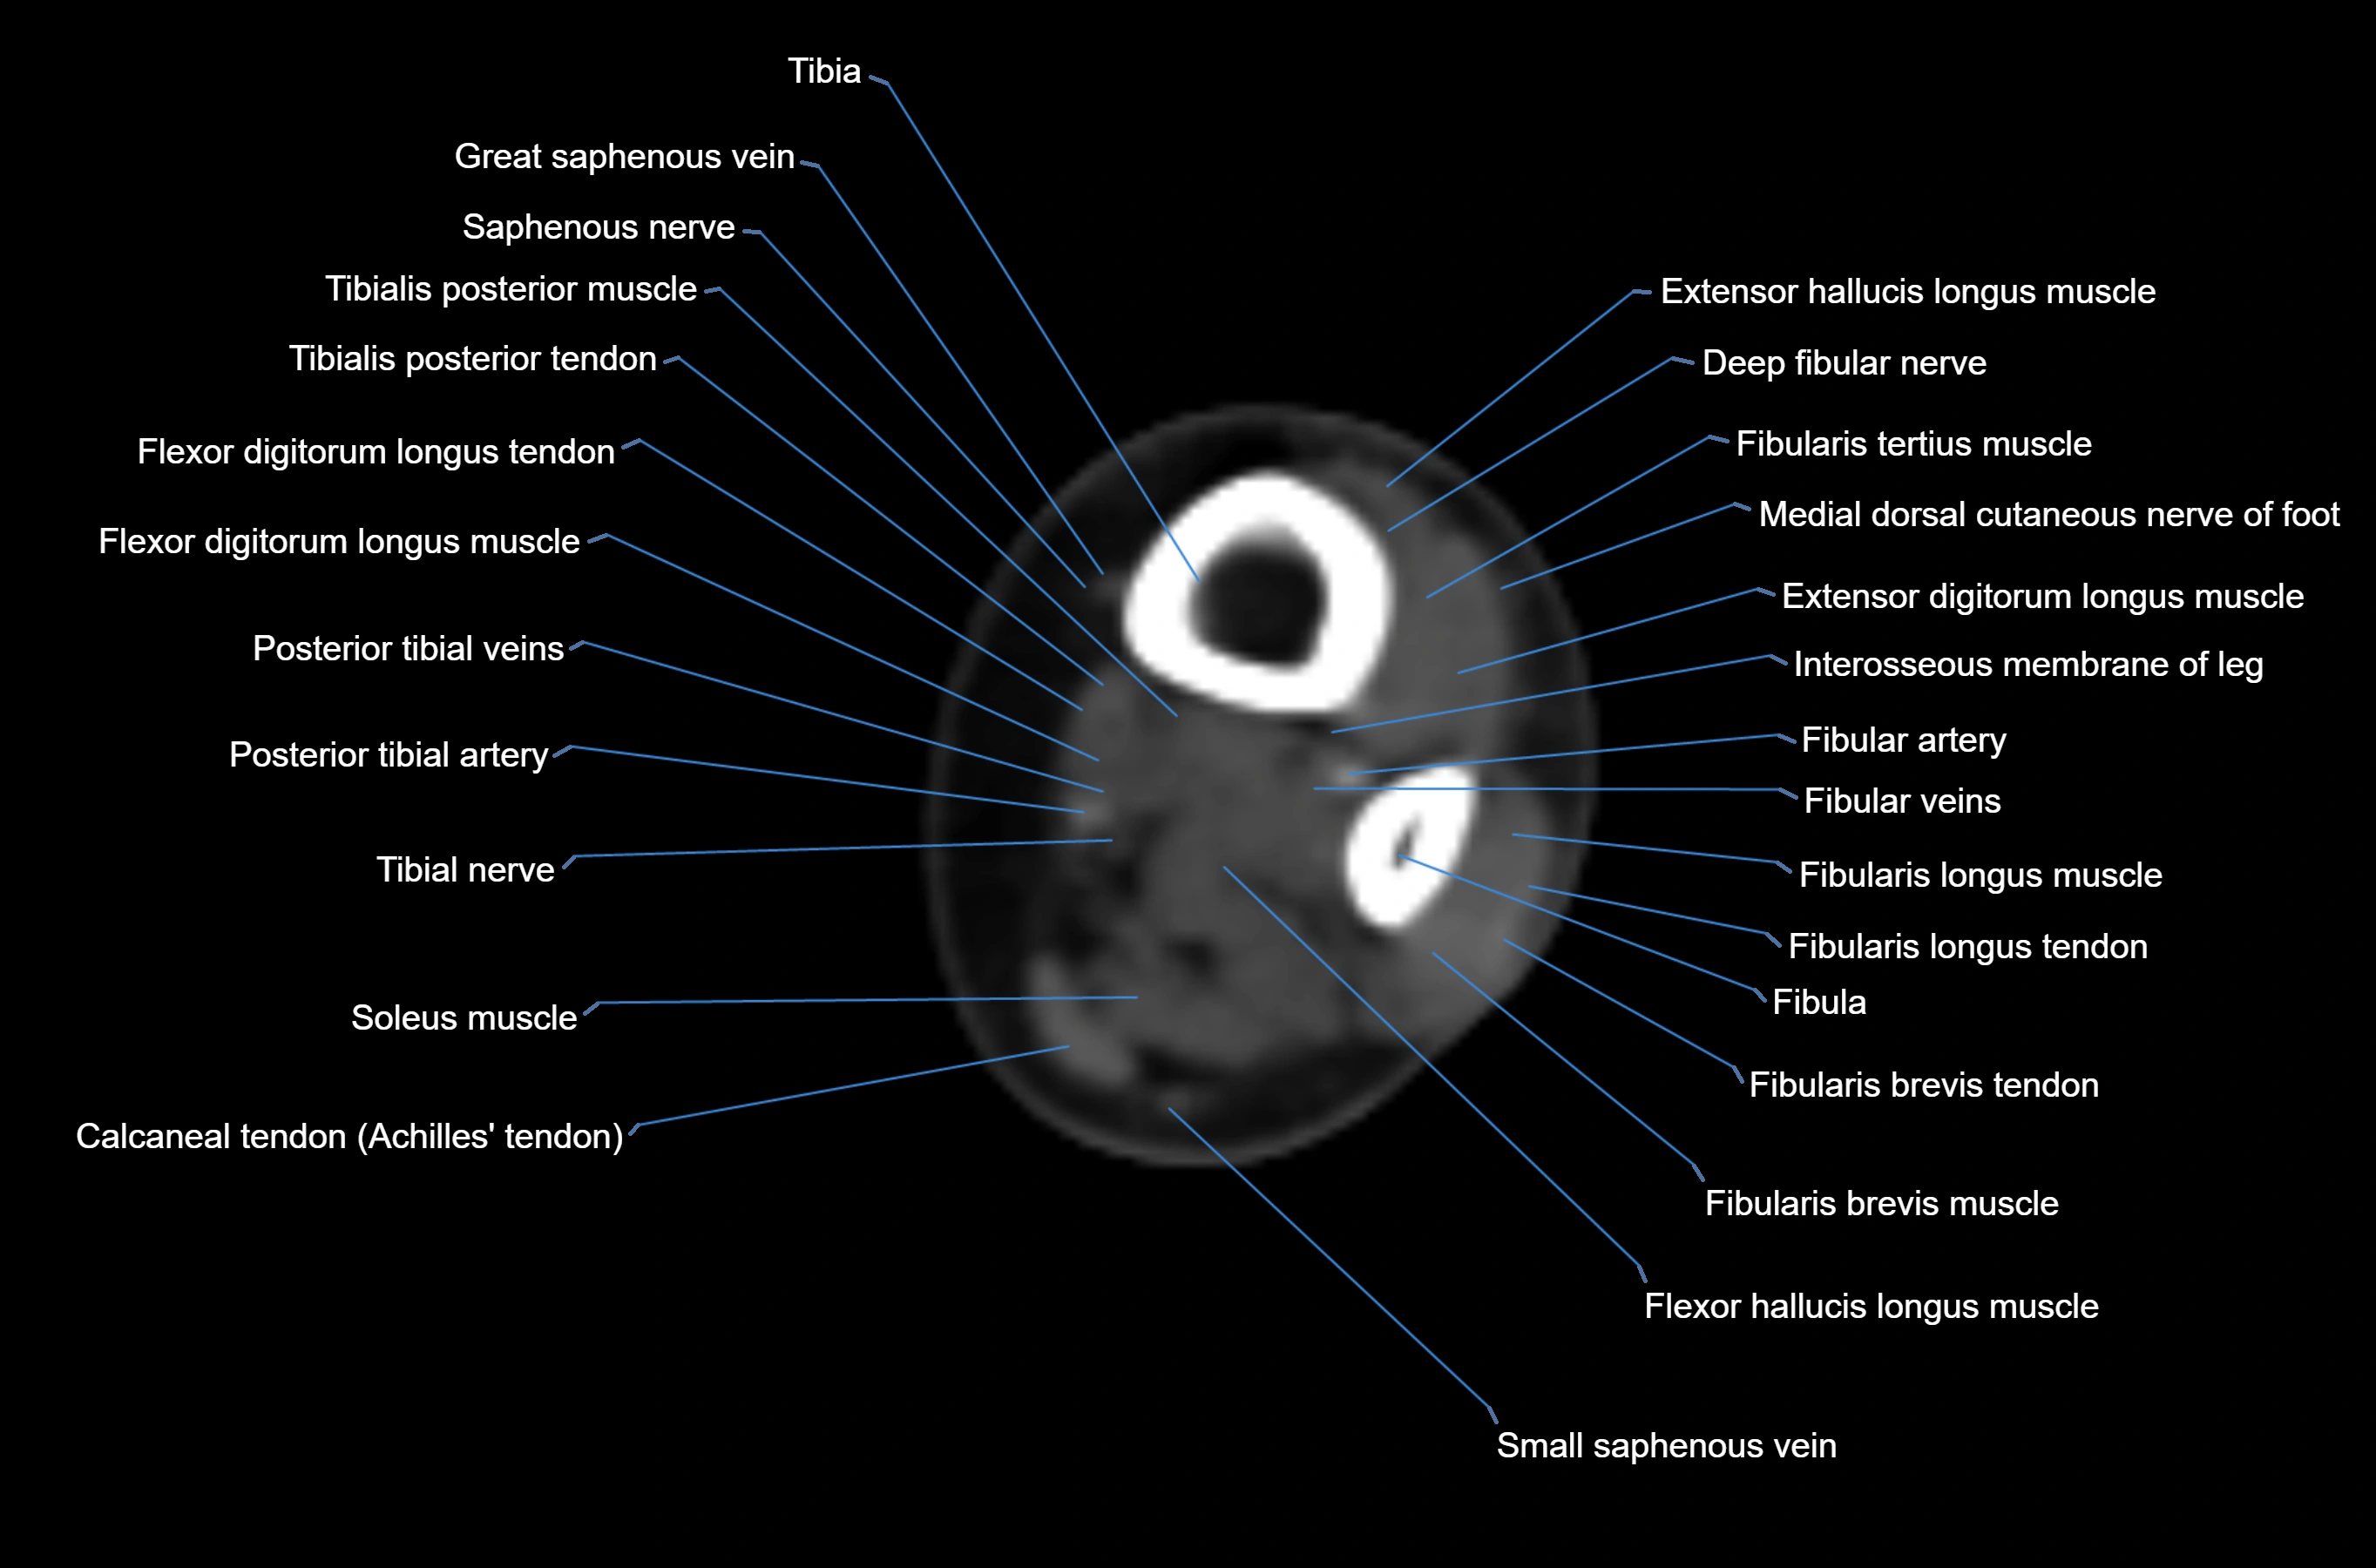

CT image